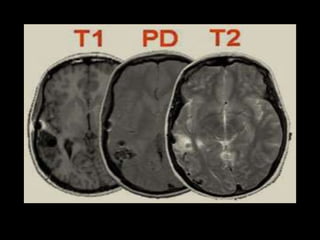

T1 E T2

NÃO ESQUECER !!!! T1-ANATOMIA E T2-

PATOLOGIA

DENSIDADE DE PRÓTONS (DP)

NÃO ESQUECER !!!!T1-ANATOMIA E T2- PATOLOGIA